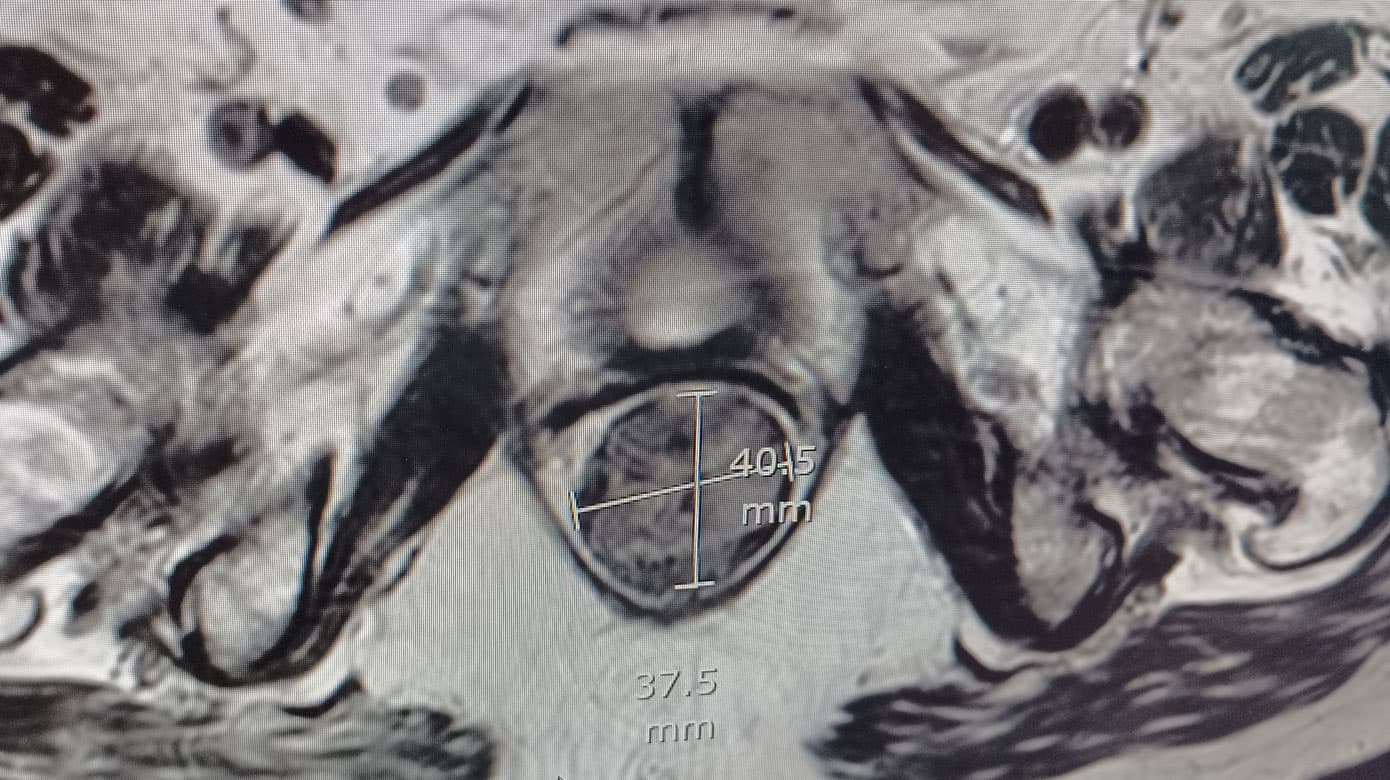

Hun blev diagnosticeret med en GIST på 7 cm i diameter i rectum og fik foretaget biopsi ved transrektal UL-skanning. Biopsien var uden mitoser, og mutationsanalysen viste en deletion i receptor KIT exon 11. Patienten fik imatinib 400 mg × 1 dgl. for at reducere tumorstørrelsen, men fik svære hudbivirkninger, og behandlingen blev skiftet til nilotinib, en andengeneration-TKI. Efter ni måneders behandling var der opnået 40% tumorreduktion. Tumoren målte nu 4 cm i diameter og muligheden for kurativ kirurgi blev revurderet. Patienten var fortsat alment svækket, klassificeret som ASA 3, og hun blev derfor ikke vurderet til at være egnet til kirurgi, hvorfor behandlingen med nilotinib fortsatte. Et år senere var der bedring i patientens almentilstand, mens tumorstørrelsen fortsat var 4 cm i diameter (Figur 1). Efter i alt 20 måneders behandling med TKI fik patienten foretaget transvaginal resektion af GIST. Der blev lavet en miniepisiotomi på begge sider af vagina og en Lone Star APS retractor blev placeret. Herefter blev vaginalvæggen incideret, og tumoren blev fridissikeret med LigaSure og fjernet uden brud af kapslen, inkl. adhærent rectumslimhinde. Herefter lukkedes defekten i rectum, septum rektovaginale samt vaginaslimhinden lagvist med resorberbare suturer.